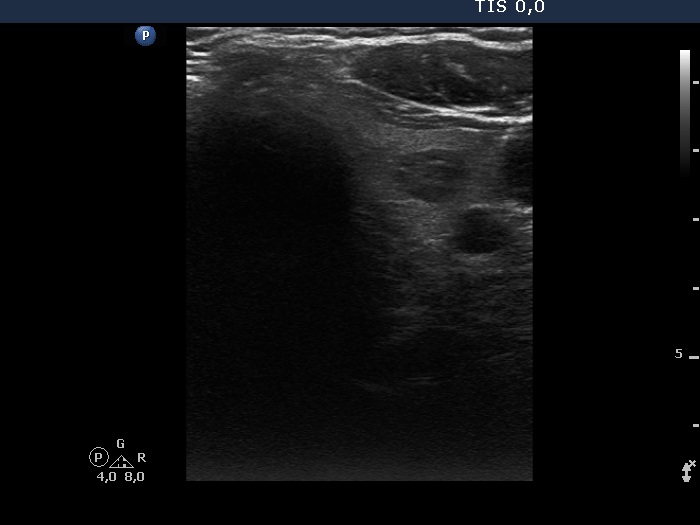

Ultrasonography. The right lobe was greatly enlarged and had numerous nodules. The lower pole could not be visualized during swallowing. The left lobe had a small, moderately hypoechoic nodule.

Neck and upper mediastinal CT scan were performed which showed that the right lobe spread almost 11 cm below the level of the clavicle.